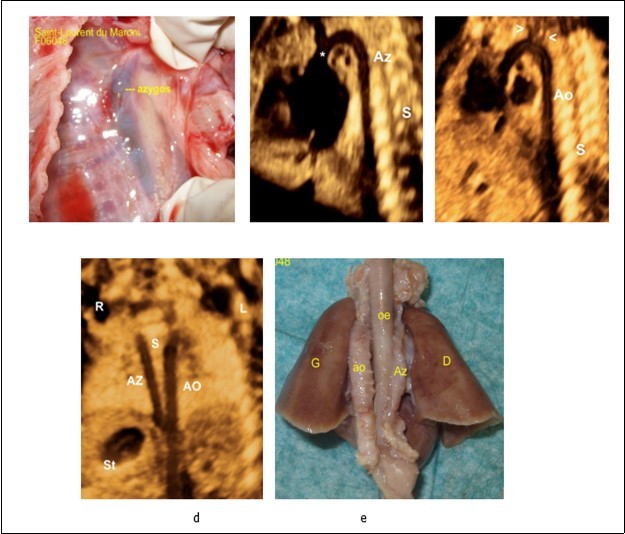

In our study, three patients had an interruption of the IVC (Figure2 b, c), the first patients had severe cardiac malformation and 2 patients had a persistent left superior vena cava (LPSVC) (Figure 4 a, b). The four patients had ultrasonographic signs for situs ambiguous (left isomerism) and in 3 of them the diagnosis was confirmed by fetopathological examination. The first patient had an unfavorable outcome (pregnancy termination “hydrops foetalis”) and this was linked to severe heart disease. The second case with no sever cardiac malformation delivered at 27+6 weeks’ gestation and child had psychomotor retardation which appears to be related to extreme prematurity. All the three karyotypes were normal, research 22q11 microdeletion was negative. " Double vessel sign " was found in all cases with interruption of the IVC with azygos continuation -VCI. (Figure 3 b, c). Grayscale facilitated the diagnosis of situs (Figure 1). Power Doppler imaging contributed primarily to prenatal diagnosis of vascular anomalies, and it was beneficial in detecting situs (Figure 2). 3D ultrasound and Doppler enhanced the visualization of fetal vessels. Using volumes, meticulous offline evaluation can be performed, enabling the operator to reconstruct fetal anatomy. 2 patients had the stomach in the right side, one of them without congenital heart disease. (Figure 1 d , 3b). Figure 5.

Figure 5.a-Fetopathological examination showing dilated azygos. b- Sagittal image demonstrating the dilated azygos vein and azygos arch connecting to the superior vena cava (*). c-Aortic arche in the same patient, the aortic arche is distinguished from the its branches (arrow heads).e-Coronal planes of the chest and abdomen in a fetus with left atrial isomerism and interrupted inferior vena cava showing the azygos vein (AzV) running parallel and posterior to the descending aorta (on both sides of the spine).f- Fetopathological examination showing azygos and aorta.

Absence of the hepatic segment portion of the IVC with azygos continuation into the right or left SVC is referred to as an interrupted IVC and it have been reported as an incidental finding at autopsy as early as 1793 by Abernethy in a 10-month-old infant with polysplenia and dextrocardia. Moller et al 18 emphasized the association, 11 and now it is considered an excellent marker for the presence of left atrial isomerism. a finding that occurs in about 80%. Therefore, a careful examination of the IVC should be performed in the suspected heterotaxy patient. 24, 28. In this condition, the venous drainage from the lower extremities reaches the superior vena cava via the azygos vein (azygos continuation) or via the hemiazygos vein (hemiazygos continuation) emptying into either a right-sided superior vena cava or into a persistent left superior vena cava. It can be recognized by the observation of the aorta and the (dilated) azygos vein on its right or left side (hemiazygos) either in the upper abdomen or at the level of the four-chamber view 31. Sheley et al 29 described it as the ‘double-vessel sign’ (Figure 3) and found it in all eight fetuses with left isomerism that they examined, but also in one false-positive case with right isomerism. If the examiner is aware of this sign, he can easily detect it prenatally on real-time imaging and confirm it using color Doppler. Three of our patients presented this sign (Figure 3), care should be taken not to confound it with other conditions that mimic a ‘double-vessel sign’, for example, esophageal duplication cyst, that can be confound with a dilated azygos vein in 4 chamber view, color doppler can differentiate between the two conditions. (Figure 3 d, f).